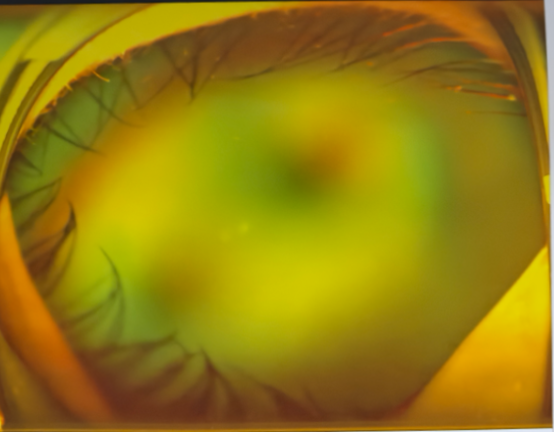

左眼术前△

左眼术后△

视网膜脱离.png